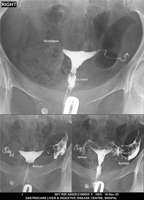

Section: HSG

Total: 49 Cases